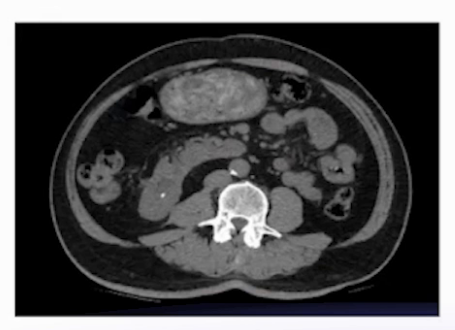

泌尿系CT平扫:右肾下盏有6mm小结石。

术中发现三个关键问题:①肾盂内尿液浑浊;②使用钬激光碎石时,结石呈丝状且藕断丝连,难以打成颗粒;③结石实际大小远超CT所示的6mm,超过2cm。

术前B超显示:右肾上盏有一颗21mm×30mm的大结石,与CT所见不符。

2周后,鉴于患者结石负荷大,行B超引导下经皮肾镜取石术。该结石为X线及CT阴性结石,成功穿刺右肾上盏后,打造影剂显示集合系统有明显充盈缺损,结石表面黄褐色。使用气压弹道轻易击碎结石,并通过负压吸引取出。

患者有右侧肾部分切除术病史,CT提示的结石大小与术中实际发现不一致,超声检查结果与实际结石负荷更吻合;术后结石成分分析确诊为氰基丙烯酸酯,该成分与患者肾部分切除术中用于止血、减少尿外渗的粘合剂相关,属于临床罕见结石类型。

本例患者诊疗的关键难点在于,其一是术前影像学评估存在偏差,CT虽为结石检查的“金标准”,但本例中未能准确反映结石实际大小,需警惕特殊病史患者的检查局限性;其二是结石处理难度大,该类粘合剂成分结石质地坚硬,软镜下激光碎石难以奏效,最终通过经皮肾镜直接击碎取出,提示特殊成分结石需针对性选择手术方式。